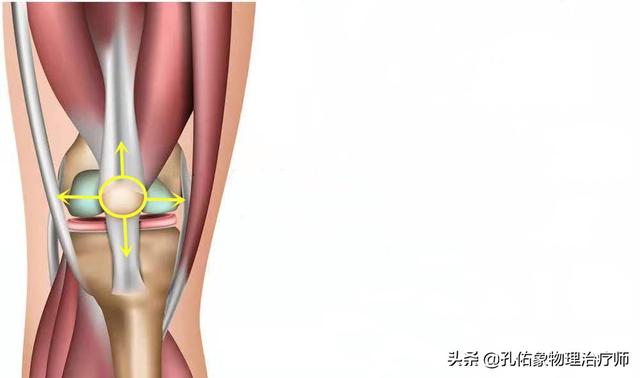

Klappern der Kniegelenke bei Streckung und Kontraktion

Wenn wir das Knie strecken, werden wir feststellen, dass sich die Kniescheibe mit der Beugung und Streckung unseres Kniegelenks bewegt, und das Geräusch, das entsteht, wenn das Gelenk gebeugt und gestreckt wird, hängt tatsächlich mit der Bewegung der Kniescheibe zusammen. Unterhalb der Kniescheibe befindet sich ein so genannter infrapatellarer Fettkörper, der ein wichtiger Teil der Struktur der Kniegelenksstreckung ist. Der infrapatellare Fettkörper hat eine dämpfende Wirkung bei der Bewegung und sorgt dafür, dass die Kniegelenksstreckungsbewegung reibungslos verläuft.

Im Allgemeinen kann diese Art von Struktur bei wiederholtem Gebrauch des Kniegelenks zu einer gewissen Abnutzung führen, die sich auf die Bewegung auswirkt, was sich unter anderem in einem klappernden Geräusch äußern kann.